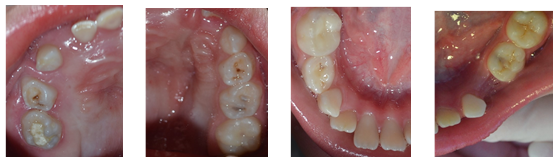

The examination of the oral cavity (Fig. 2, 3, 4, 5, and 6) showed no mucous membrane lesions. It showed atresia of the upper dental arch with right unilateral crossbite and anterior open bite. The examination also showed the widespread presence of microbial biofilm on dental surfaces and gingival bleeding, a root residual in tooth 74, a temporary restoration in poor condition on the occlusal and lingual faces of tooth 85, as well as active microcavitated dental caries lesions on the occlusal face of teeth 26, 65 and 75.

Figs. 2, 3, 4, 5, and 6: Initial clinical aspects; arch and hemiarch of the oral cavity at the beginning of the treatment